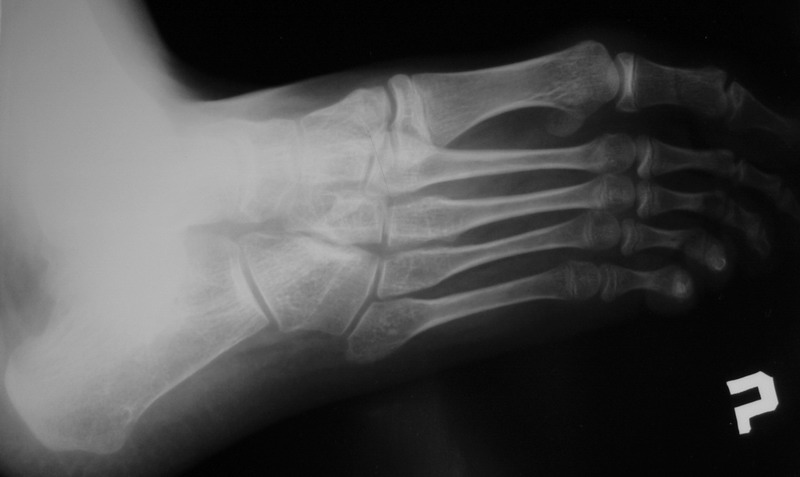

Пациент 15 л., болезнь Литтля, спастический нижний парапарез, интеллект высокий. Ребенок настроен на активный образ жизни. С недавнего времени начал ходить без дополнительной опоры. Появилась проблема с левой стопой - во время ходьбы опора приходится на смещенную кнутри таранную кость.

Может образоваться болезненный натоптыш или язва.Общепринятой операцией является трехсуставной артроде с мобилизацией таранной кости. Выполнять такую операцию у спастика и в раннем возрасте проблематично. Родстьвенники тем более готовы материально и морально осуществить хирургическое лечение за рубежом, если оно показано и возможно.Предпочтительно в Австрии и Германии. Если кто-то посоветует координаты таких клиник - были бы признательны.

В приводимом случае, 15 летнему больному показан 3-суставной артродез. Однако считаю нецелесообразным существенно менять конфигурацию стопы, поскольку плоско-вальгусные деформации стоп это компенсаторный ответ на сгибательно-приводящие установки нижних конечностей. Изменение положения стоп(коррекция пронации) может нарушить сложившийся стереотип ходьбы, и ухудшить ситуацию.

1. in spastic flat foot deformity which is not fixed but passively stretchable in a normal position it´s possible to perform the calcaneal lengthening (Evans)

2. in fixed spastic flat foot in adolescent and adults you have to perform the correctice triple arthrodesis.

This is typical deformity for spastic diplegia in CP .In 15 years old boy the best option is tripple arthrodesis .